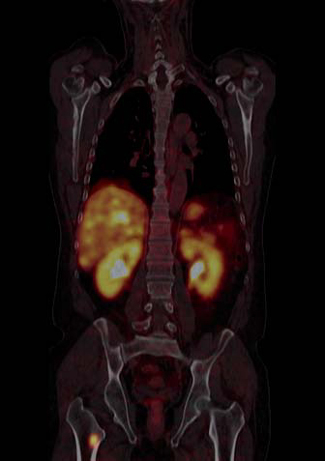

Tumores gastroenteropancreáticos

Este grupo (GEP) constituyen un grupo heterogéneo de tumores neuroendocrinos del estómago, páncreas e intestino. El más frecuente es el tumor carcinoide. El tratamiento primario es la cirugía aún en los pacientes con enfermedad metastásica, debido a que la resección parcial puede mejorar la calidad de vida, sobrevida y estado funcional. Las imágenes cumplen un papel importante para determinar la extensión de la enfermedad al inicio y en el seguimiento. Los estudios realizados con 111In pentatreotide muestran elevada sensibilidad para la detección de GEP a excepción del insulinoma. La sensibilidad para el gastrinoma metastásico, carcinoide y otros GEP son generalmente sobre 80% hasta 94%. La sensibilidad para la enfermedad metastásica tiende a ser superior a la de los tumores primarios (Figura 1) y en muchas ocasiones se encuentran lesiones no detectables por imágenes anatómicas. Utilizando Ga68 análogos de somatostatina se han obtenido excelentes resultados, con sensibilidades entre 82-100% (Figuras 2 y 3). El FDG tiene baja sensibilidad para la detección de estos tumores de lento crecimiento, bien diferenciados y bajo Ki-67, en cambio las imágenes con análogos de somatostatina presentan un patrón opuesto (Figura 4 y 5). Los tumores neuroendocrinos indiferenciados y agresivos presentan marcada avidez por la glucosa y pobre expresión de receptores de somatostatina y viceversa. Se ha visto que los pacientes con tumores con mayor expresión de Ki-67 evolucionan peor que aquellos con bajo Ki-6715. Los tumores neuroendocrinos que captan FDG tienen por lo tanto peor pronóstico16. En un estudio que comparó el rendimiento de cintigrafía con Octreoscan y FDG en pacientes con tumor carcinoide encontró que el 86% de los tumores primarios se localizaban con pentatreotide mientras que sólo el 57% con FDG. Pacientes con metástasis, el 69% fue positivo con el análogo de somatostatina, 47% con FDG y 56% con imágenes anatómicas17. Figuras similares se han obtenido con el uso de PET y Ga68análogos de somatostatina18,19.